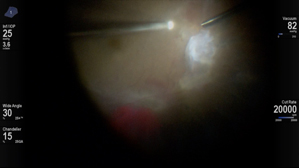

HYPERVIT Dissection

Kourous A. Rezaei MD